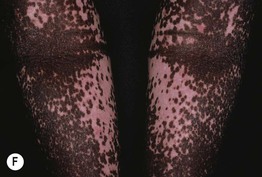

• A later cutaneous finding is leukoderma of the shins with follicular pigmentation, resembling leopard skin (Fig. 54.20).

Fig. 54.20 Onchocerciasis (leopard skin). Depigmentation of the shin with follicular repigmentation or retention of perifollicular pigment, a common site for the associated leukoderma. Clinically resembles repigmenting vitiligo or the leukoderma of scleroderma. Courtesy, Jean-Paul Ortonne, MD.

• DDx: atopic dermatitis with postinflammatory depigmentation, or atopic dermatitis plus vitiligo with Koebner phenomenon.